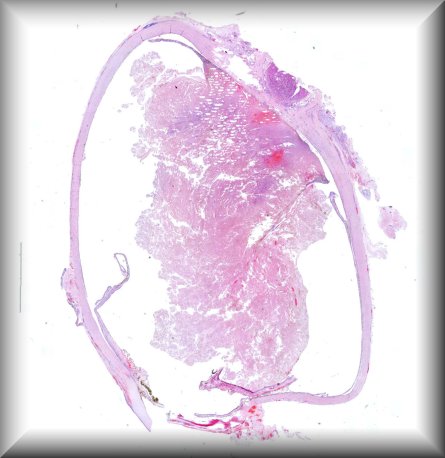

Luis Alfaro (Valencia): Rapidly growing tumour in a 51-year-old male affecting the orbit and involving the eyeball. Extended exanteration was performed, towards the skull and left facial region. Protocol |